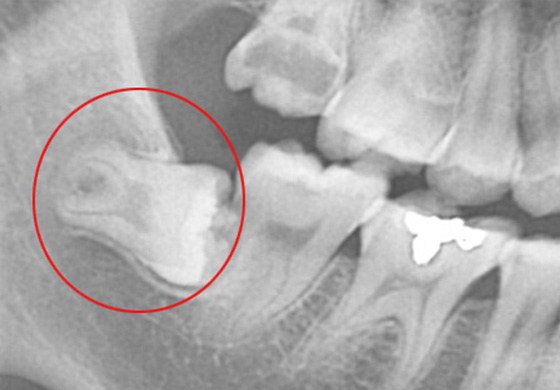

매복 사랑니는 턱뼈에 공간이 충분하지 않아 사랑니가 잇몸을 뚫고 맹출되지 못하고 치조골 내에 매복된 것을 말합니다. 이 매복사랑니는 치아가 완전히 맹출되지 않았기 때문에 음식물이 사랑니 잇몸 하방으로 고이게 되고, 칫솔질로도 제대로 제거되지 않아 잇몸 염증을 유발하여 사랑니는 물론 인접치아에까지 손상을 입힐 수 있습니다.

이 때문에 매복 사랑니는 발치를 하는 것이 가장 좋습니다. 솔트치과에서는 엑스레이 장비, 첨단 CT 등 사랑니 발치 진단에 필요한 첨단 장비를 보유하고 있어 안전하게 사랑니 발치가 가능합니다.